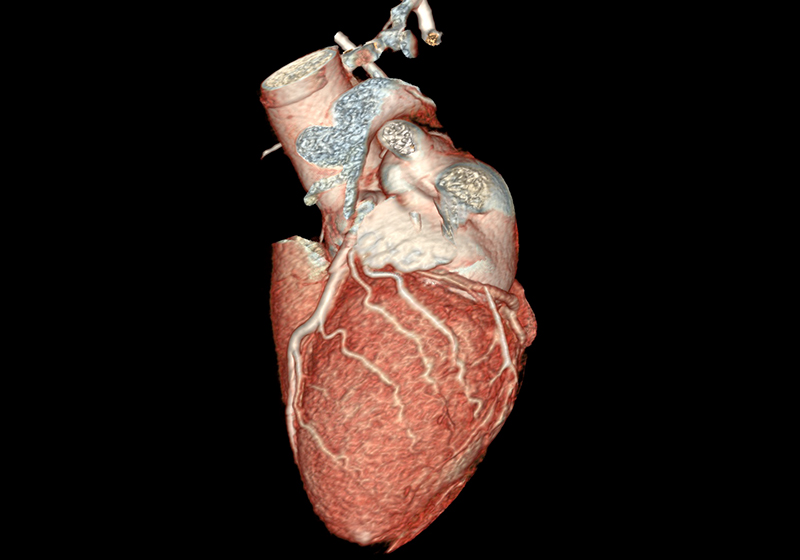

Über eine 3D-Nachverarbeitung werden die Herzkranzgefäße sowie eventuelle Engstellen und Verkalkungen dargestellt und vermessen. Sofern vorhanden, können an dieser Stelle auch Stents oder Bypässe auf deren Durchgängigkeit überprüft werden.